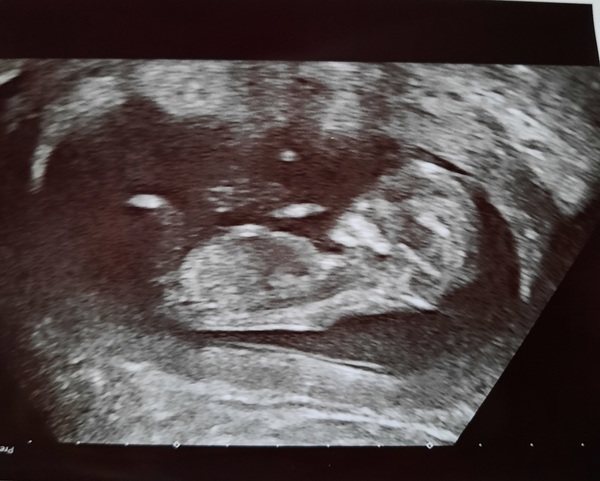

Hello all 😊 Well that was exhausting, I was very anxious before and the appointment was long! By the time they scanned me, did all the bloods, went through my history, it was nearly 2 hours (including a 45 min delay, but let's not talk about that).

My son is fine 😊 He is a little wriggler, it's confirmed now, today he was waving at us and the sonographer 😂 So excuse an odd angle but since he was upside down (!) I had to flip the photo 😂 He's measuring ahead again, so we have an official EDD brought forward to 12 August 💙

As expected, I will be consultant led. I already have my 16 week appt and 20 week scan booked, I will also see my consultant in-between. DH was sobbing again, bless his heart 💙

Congratulations @PurplePansy05, what a gorgeous scan photo! So delighted for you that you get to tell everyone now, must feel wonderful. Also sounds like your DH is so lovely, very happy for you both! x

@PurplePansy05 what a gorgeous scan - he looks perfect even if he was upside down! I was getting all emotional reading your post so I can't even imagine how you're feeling. So amazing hearing you say your son! It feels very real - I still catch myself saying 'it' and then feeling bad 😂